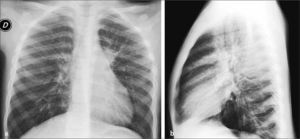

En los niños este compromiso se observa predominantemente en infecciones bacterianas. Desde el punto de vista anátomo-patológico, la neumonía corresponde a un compromiso inflamatorio del parénquima pulmonar en el que los alvéolos, normalmente llenos de aire, se rellenan con detritus y secreciones lo que radiológicamente hace aumentar la densidad del parénquima comprometido; puede ser inicialmente disperso y con escasa tendencia a la focalización, determinando inicialmente opacidades tenues, únicas o múltiples. La consolidación neumónica puede requerir hasta 24 horas para tener una adecuada representación radiológica, por lo que exámenes muy precoces pueden originar falsos (-) en el diagnóstico (4). Cuando el compromiso progresa, se evidencian conglomerados densos que pueden constituir la clásica neumonía lobar o también áreas confluentes, parcheadas, focales uni o bilaterales, descripción que se ha utilizado como equivalente al concepto de bronconeumonía, término que actualmente se considera ambiguo por lo que se recomienda referirse a estas alteraciones como “compromiso alveolar multifocal” (4) (Figura 3).

La persistencia de aire en los bronquios adyacentes a las áreas condensadas produce el signo clásico de “broncograma aéreo” en el espesor del foco denso que aparece surcado por imágenes aéreas ramificadas, imagen que puede también observarse en atelectasias.

En el análisis de las Rx de tórax de los niños es importante observar cuidadosamente los hilios, el área retrocardíaca y las bases pulmonares (proyectadas retrodiafragmáticas en placas frontales), que corresponden a sitios en que se localizan las neumonías denominadas escondidas (Figura 4).